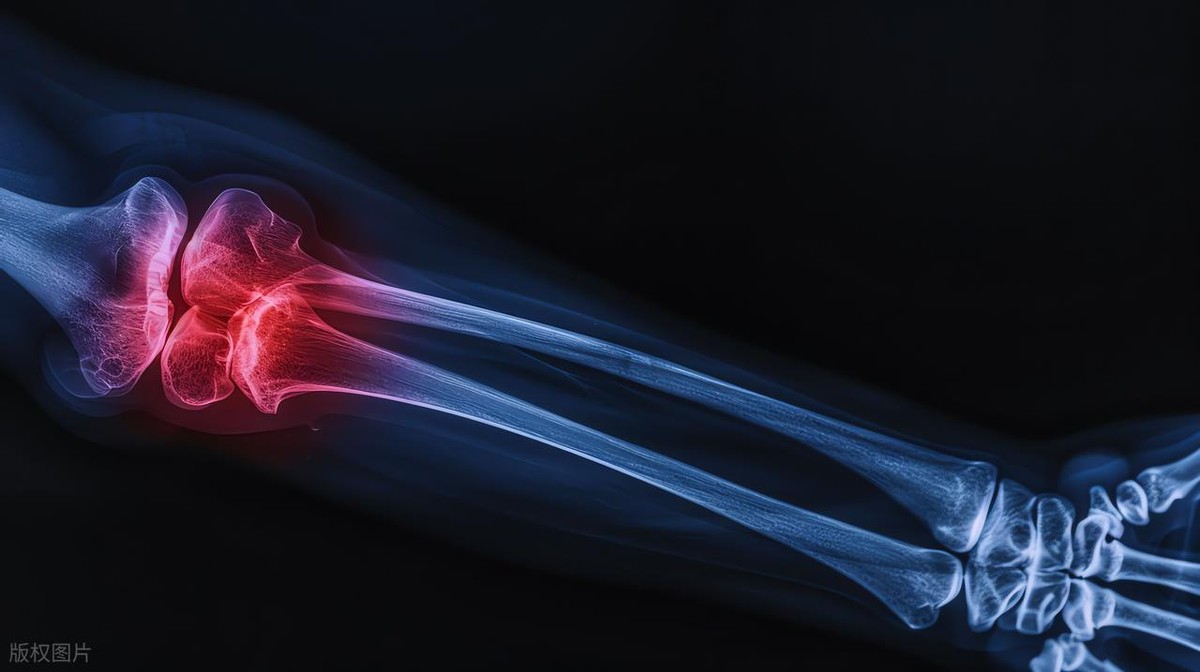

为什么医生总说日常小习惯累积,才是关节损伤的最大元凶?关节就像身体的“轴承”,骨头末端的软骨负责缓冲减震,关节滑液起到润滑作用,韧带、肌肉则负责固定和支撑,这套结构精密又脆弱,需要长期温和养护,最怕反复、持续的不良刺激。

关节本身没有痛觉神经,早期磨损时根本感觉不到疼痛,等出现酸胀、刺痛时,软骨已经磨损到一定程度。这就是为什么医生反复强调,日常习惯决定关节寿命,比起突发损伤,日积月累的坏习惯,才是摧毁关节的“头号杀手”,也是最容易被大家忽视的。